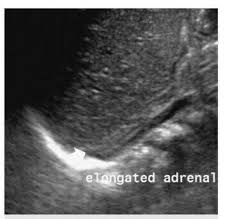

Kidney Ultrasound Adrenal Glands. It s hard to see normal adult adrenals on ultrasound despite being near the kidneys review of the adrenals in an adult is not part of the routine kidney ultrasound. An outer cortex and an inner medulla.

Ct scans also show the organs near the adrenal glands as well as lymph nodes and distant organs. 190 layers of adrenal gland. It s hard to see normal adult adrenals on ultrasound despite being near the kidneys review of the adrenals in an adult is not part of the routine kidney ultrasound.

Details of the adrenal glands. High resolution real time sonography allows visualization of normal adrenal glands in 71 92 of adults. The normal ascent of the kidneys allows the organs to take their place in the abdomen below the adrenal glands. The left adrenal gland is imaged by a posterolateral approach in coronal plane through the long axis of the left kidney.